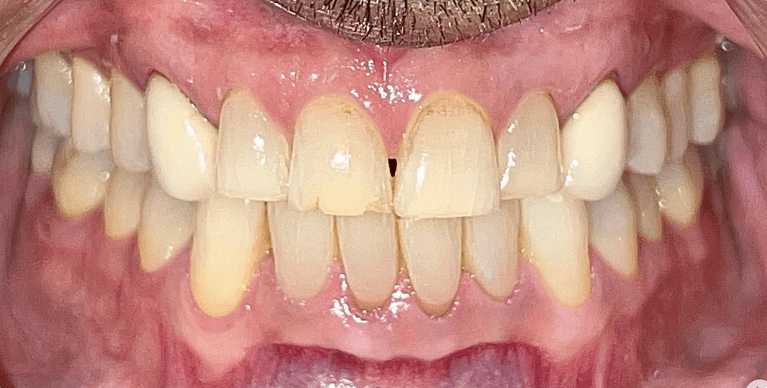

Upper & Lower, All on 4 fixed implant teeth with finals. Patient went home with temp fixed teeth the same day.